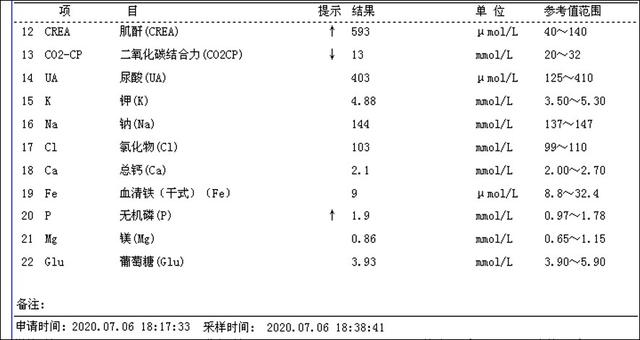

治疗前甲状腺旁腺素非常高(3300pg/ml),血钙正常,超声显示双侧甲状腺旁腺明显增大(如下图),核素扫描显示甲状旁腺功能亢进性骨代谢异常性骨病(骨骼变形)。